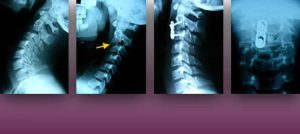

Institut Chiari & Siringomielia & Escoliosis de Barcelona is highly specialized neurosurgical center dedicated to the diagnosis and treatment of spinal and brain disorders, with a focus on the clinical concept of Filum Terminale Disease. Conditions treated include: